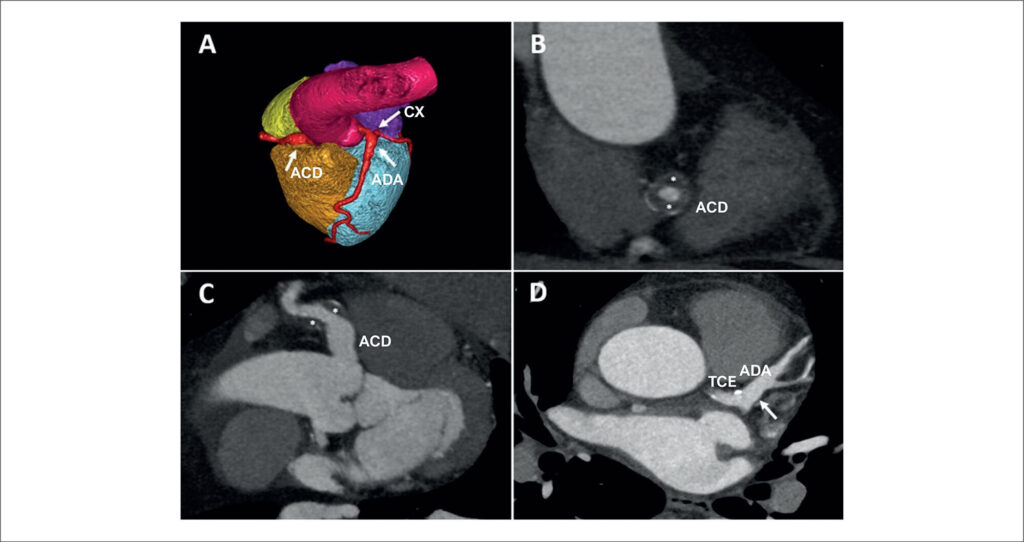

Um paciente de 54 anos, sem histórico médico prévio, foi avaliado na clínica de cardiologia por dor torácica com características atípicas. Devido a uma probabilidade pré-teste de cardiopatia isquêmica de 20%, foi realizada tomografia computadorizada de coronárias, que evidenciou um aneurisma coronário (10 × 11 mm) desde a origem da artéria coronária direita (ACD) até o segmento médio (, seta branca; ). No segmento médio da ACD, havia trombose circunferencial parcial com estenose luminal de 50% ( e ; , asteriscos brancos). O restante da ACD não apresentou obstrução da artéria coronária. Também foi observado um aneurisma de 9 × 9 mm no tronco da artéria coronária esquerda, estendendo-se até a bifurcação e porção proximal da artéria coronária descendente anterior, sem lesões significativas ( e , setas brancas; ). Foi observado também um aneurisma de 5 × 6 mm na artéria circunflexa esquerda proximal, sem lesões coronárias significativas (, seta branca; ). Foi realizada ressonância magnética cardíaca sob estresse com regadenoson, que foi negativa para isquemia induzida. Sorologias e autoanticorpos, também solicitados, foram negativos. Optou-se por iniciar tratamento clínico com ácido acetilsalicílico e atorvastatina. Durante o acompanhamento de 6 meses, o paciente não apresentou desfechos coronários e permaneceu assintomático.